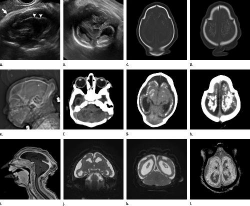

The latest research, published in the journal Radiology, draws from

imaging and autopsy findings linked with confirmed Zika infections

done on 17 infants and fetuses cared for at the Instituto de

Pesquisa, in Campina Grande in the state of Paraiba in northeastern

Brazil, where the infection has been especially severe.

Nearly all babies in each group had ventriculomegaly, a condition in

which the ventricles, or fluid-filled spaces in the brain, are

enlarged.

While most of the fetuses had at least one exam showing abnormally

small head circumference, suggesting they had microcephaly, three of

the fetuses with ventriculomegaly had normal head circumference, but

severe ventriculomegaly.

Nearly all of the fetuses or babies in the confirmed Zika group and

nearly 80 percent of those in the presumed Zika group also had

abnormalities of the corpus callosum - a large bundle of nerves that

facilitates communication between the left and right hemispheres of

the brain.

In all but one of the cases studied, the researchers found instances

in which developing neurons did not travel to their proper

destination in the brain.

In many cases, the babies' skulls seemed to have collapsed on

themselves, with overlapping tissues and abnormal skin folds

suggestive of a brain that had stopped growing.

"From an imaging standpoint, the abnormalities in the brain are very

severe when compared to other congenital infections,” said study

co-author Dr. Deborah Levine of Beth Israel Deaconess Medical Center

and a radiology professor at Harvard Medical School.